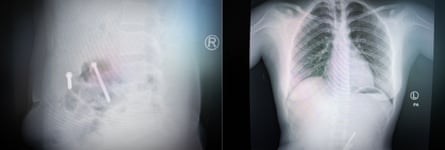

The objects, revealed by X-ray and surgically extracted by doctors more than two years later, were forced inside Tseneat as she lay unconscious after being gang-raped by six soldiers.

She is one of tens of thousands of Tigrayan women subjected to the most extreme forms of sexual violence, in attacks designed to destroy their fertility. Medical records and X-rays obtained by the Guardian and reviewed by independent medical specialists show a pattern of cases where women have had foreign bodies forced into their reproductive organs, including nails, screws, plastic rubbish, sand, gravel and letters. Under international law, it is genocide to destroy fertility or prevent births with the intention of wholly or partly destroying an ethnic group.

After removing the materials visible through her cervix, the staff performed X-rays to check for more foreign bodies. The image they produced is difficult to comprehend: at the centre of Tseneat’s uterus, between her hip bones, lies a pair of metal nail clippers. When they were removed, they were rusting, says Sister Roman, who treated her.

At a clinic in Mekelle, a team of nuns who provided medical care during the war maintained a single, locked cupboard where they kept a cache of evidence of the crimes against these women: X-rays, medical records, and even the objects themselves. “These foreign bodies are documented and also held in our storage – a lot of foreign bodies, anything, either plastics, metal objects, anything around them are introduced into their reproductive organs,” says Sister Mulu, who led the clinic. She leafs through X-rays, pulling out imaging of yet another abdomen – bisected by a sharp, curved metal spike and a thick bolt.

For the women who survived the insertion of objects, living with this kind of foreign body means “severe and long-lasting adverse health consequences and injuries”, says Dr Rose Olson, an internal medicine specialist and instructor at Harvard medical school, who has reviewed and commented on X-rays from the cases.

“If the object was inserted into the vagina and it was done so in a very forceful manner, it could certainly lead to a perforation or break through the tissue and then enter your abdominal cavity, and that would probably lead to very severe illness and injury,” she says.

The objects could easily remain there for years, Olson says, but would put the women at extremely high risk of “pelvic inflammatory disease, or inflammation which can lead to things like infertility and scarring, chronic pelvic pain and fistulas.”